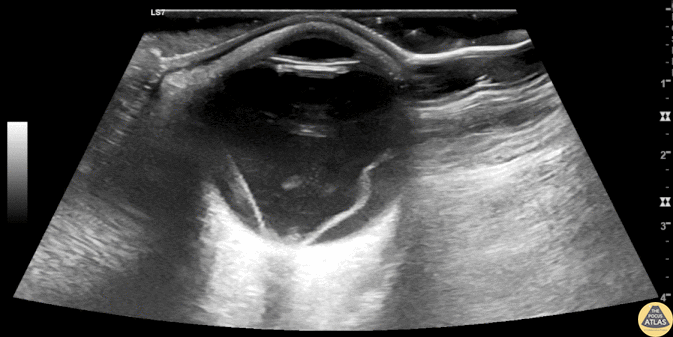

Orbital - Macula Off Retinal Detachment with Vitreous Hemorrhage

50s M with PMH cataract surgery presented with sudden onset flashing and floaters in his eye, followed by painless vision loss. His visual acuity was limited to light perception only. A still POCUS image is shown here, with an irregular hyperechoic line in the posterior chamber which is attached to the optic disc, representing a retinal detachment. Scattered hyperechoic areas are seen in the posterior chamber anterior to the retina, likely representing vitreous hemorrhage. The presentation with profound painless vision loss and retinal detachment on the medial and lateral aspects of the retina suggests involvement of the macula (“macula off” retinal detachment). This patient was evaluated by ophthalmology in the ED and was taken for operative repair. Dr. Michael Kidon, PGY4 Denver Health Residency in Emergency Medicine